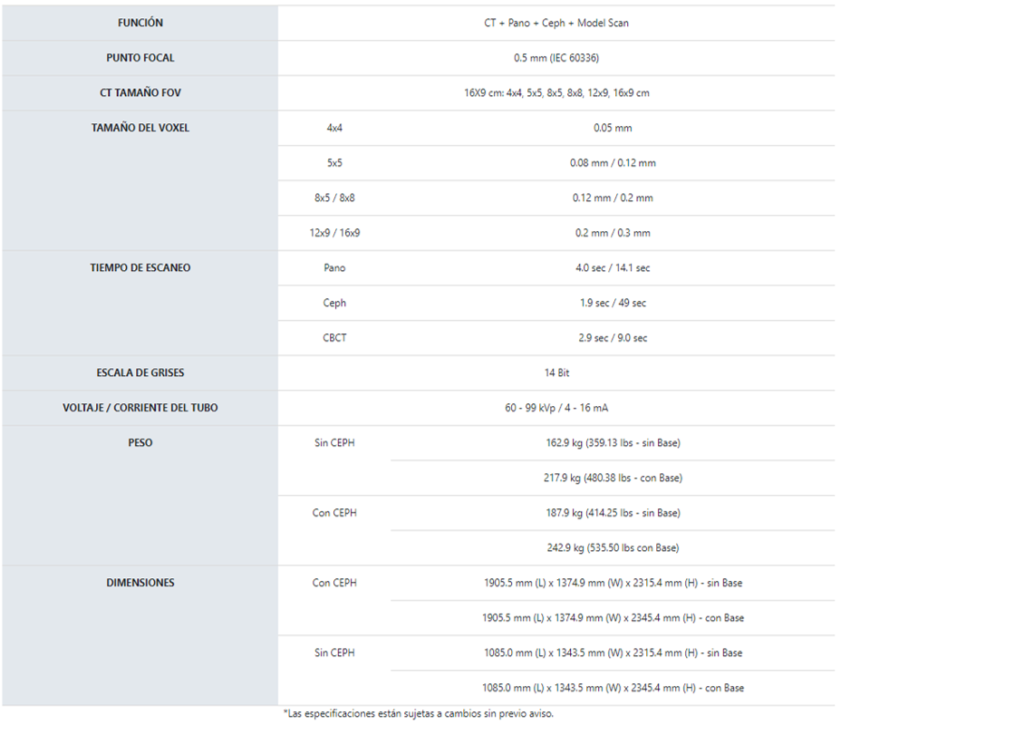

ESPECIFICACIONES